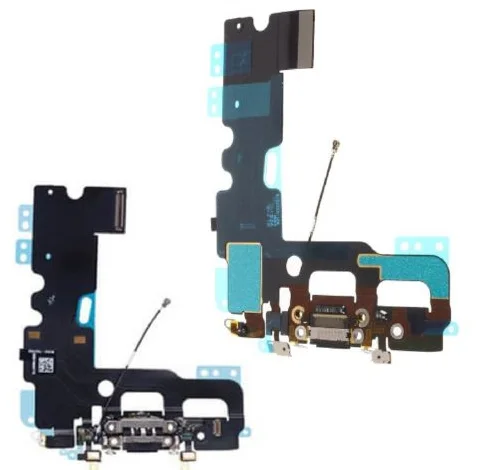

Scintillator | CsI |

Chip type | CMOS APS |

Pixel Pitch (μm) | 9.19M(2524*3640) |

Line resolution | ≥ 10lp/mm (actual value) |

Effective area | 46.7*67.3mm |

Dimensions | 77.1*53.8mm |

Operating System | Windows 7/10/11 (32&64 bits) |

Compatibility Protocol | TWAIN |